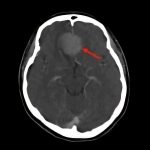

断層撮影

手術前2

摘出 後